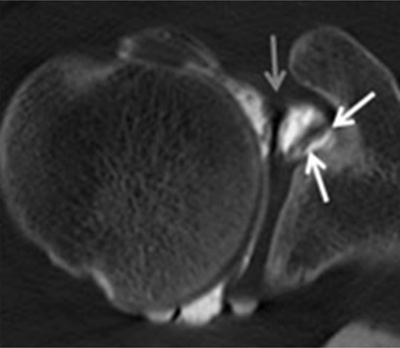

Figure 19

Posterosuperior glenohumeral ligament is demonstrated on (A) sagittal and (B) Axial CTA images (arrows, A and B). It arises from the posterosuperior part of the glenoid neck, medial to the posterosuperior labrum and the origin of the long tendon of the biceps. Laterally, it fuses with the posterior part of the rotator cable and fibers of the infraspinatus before these three structures jointly insert on the posterior facet of the greater tuberosity.